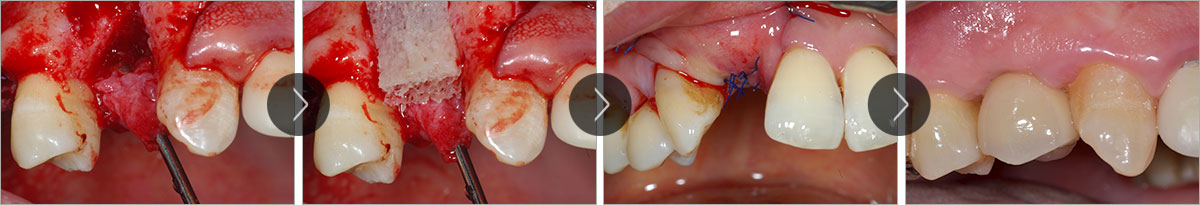

과거에 뼈이식술은 치조골 소실에 따른 심미성을 회복시켜 주기 위한 시술로 드물게 적용되었지만, 최근에는 치아 임플란트 시술의 발달로 임플란트 시술에 필요한 치조골의 확보가 어려울 경우에 광범위하게 시행되고 있습니다. 뼈 이식은 임플란트 시술부위에 치조골이 충분하지 못한 경우, 환자 자신의 뼈나 인공뼈를 이식하여 뼈의 양을 충분히 확보한 후에 임플란트 식립을 할 수 있도록 하는 시술방법입니다. 이와같은 뼈이식술은 임플란트의 성공률을 높이기 위한 부가적인 시술이라고 할 수 있습니다.